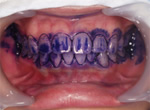

1.染出し液を塗る

歯垢がどれだけ付いているか、どの部分に残っているかを調べるために

染出し液(ニューツートン)を歯全体に塗ります。

一般には歯と歯の間、歯の裏側が染まる場合が多いです。

染出し液を塗った後にかるくうがいをします。

色が付いていない部分はきれいに磨けているところです。付いている部分は磨き残しがあるところです。

古い歯垢は青色に、新しい歯垢は赤色に染まります。

染まっている部分を見ながら歯ブラシの当て方

磨く力加減などお話しいたします